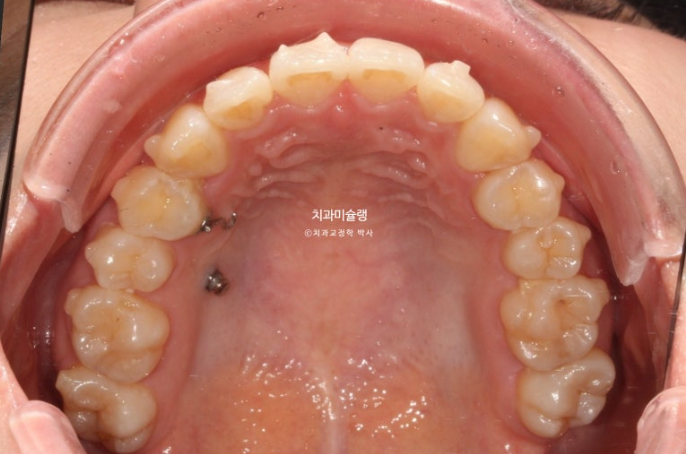

사랑니 공간을 이용하여 어금니를 뒤로 밀기 위한 교정용 나사를 입천장에 심고 진행했습니다.

중심선 불일치가 여전히 남아있으나 앞니 배열은 좋습니다.

어금니 교합도 좋습니다.

중심선과 앞니 배열을 좀 더 개선하고자 추가장치 제작에 들어갑니다.